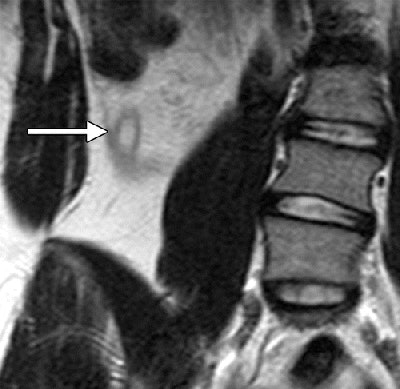

The researchers decided to compare MRI without contrast and ultrasound to see if the former was a viable alternative for pediatric appendicitis. They identified 453 patients between June 2012 and May 2013 who met the study's inclusion criteria. Of those patients, 81 (18%) underwent both ultrasound and MRI scans and were enrolled. The group consisted of 47 girls and 34 boys, with a mean age of 12.4 years (range, 4 to 17 years).

Thirty patients (37%) had pathologically proven acute appendicitis, the authors wrote. Eight had gross perforation and two had microscopic perforation, for an overall perforation rate of 33%.